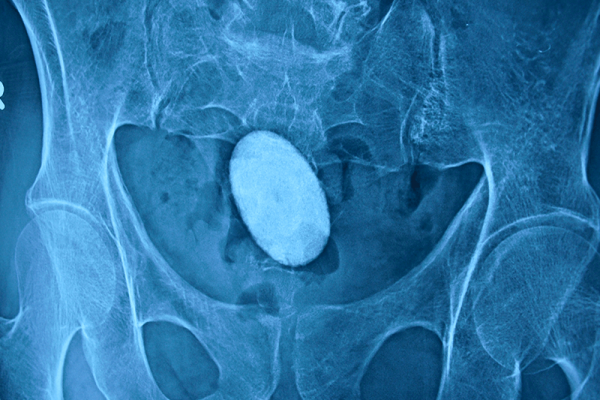

Bladder Stone Bladder stone is one of the common condition affecting both young and elderly people. It causes a lot…